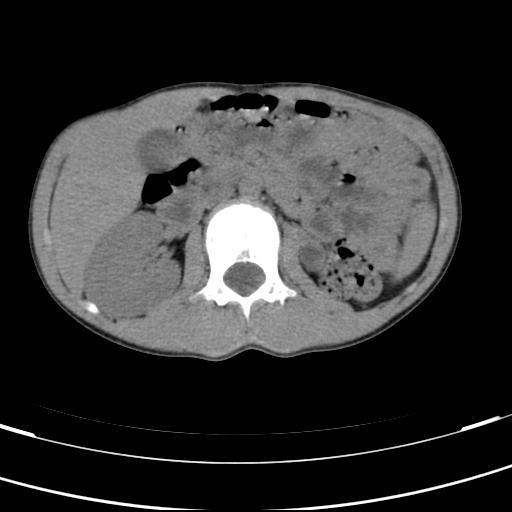

标题: PED3157:左肾缺如,请教脾脏的改变?、、

男孩,9岁。胃部不适。

左肾发育不良

脾脏位于左侧,但数个脾脏呈分离状态,左肾缺如,右肾代偿肥大。考虑多脾综合征。